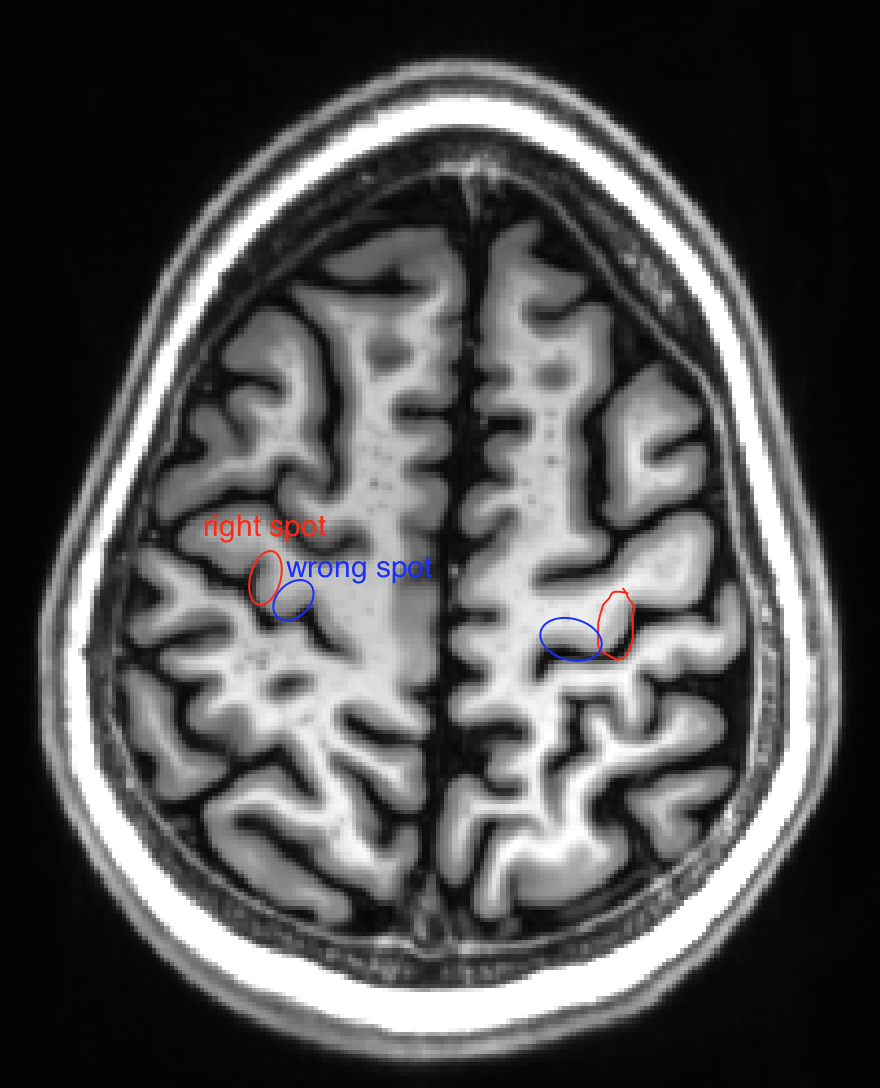

Screenshot 2018-03-20 09.56.01 renzohuber March 20, 2018March 20, 2018 Published by renzohuber View all posts by renzohuber Published March 20, 2018March 20, 2018